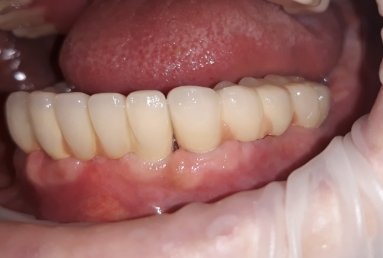

FULL ARCH FIX RESTORATION ON ALPHA BIO IMPLANTS

Our patient suffered from advanced periodontitis and we had to extract all mandibular teeth. After 2 month we inserted 8 Alpha Bio implants that healed in 4 months. All this time a full mobile temporary prosthesis was made, that was replaced in the end with fixed restorations made of porcelain fused to metal.

In the next step, tha patient wants to replace also the maxilary old mobile prosthesis with a fixed restoration.